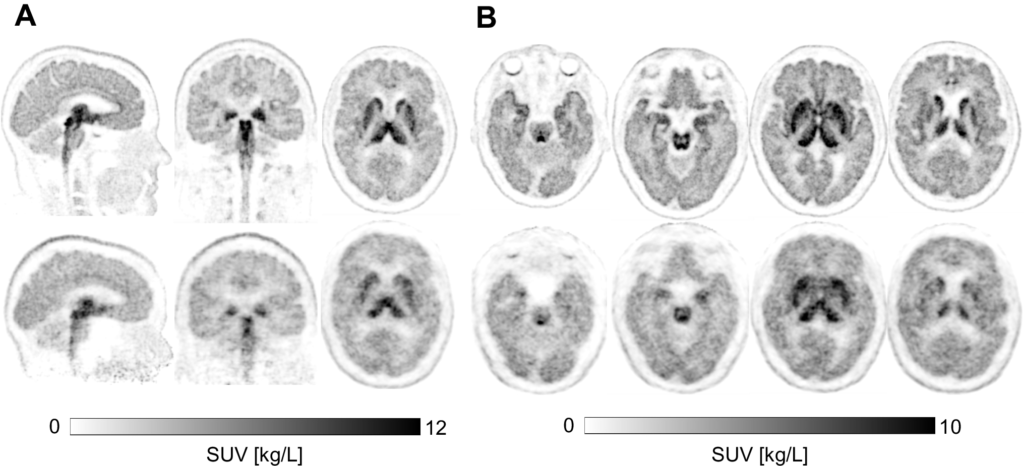

Abstract in European Journal of Nuclear Medicine and Molecular Imaging: Exceptional brain PET images from the NeuroEXPLORER: scans with targeted radiopharmaceuticals and comparison to HRRT